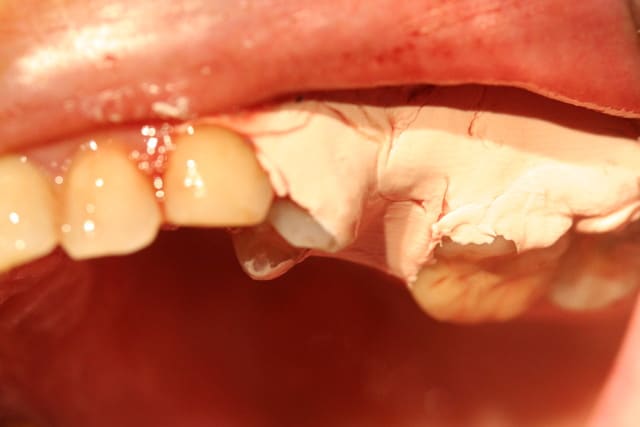

donc gouttières ou panssement supra gingivale comme coe pack